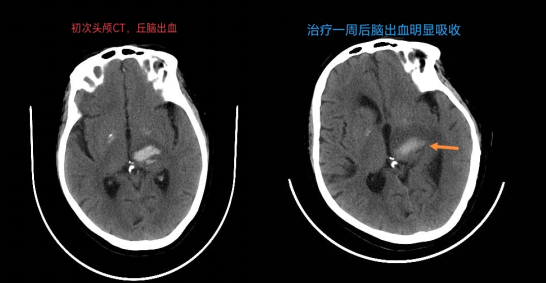

在快速完善相关检查后,神经内科医师与护理团队密切配合,刘丽芳医生评估患者出血量5ml左右,在高秀先主任的指导下予以降压、保护脑组织、补液、抑酸预防消化道出血等对症支持治疗。

经过医师的精准用药、护士们的专科护理及家属精心照顾,医务人员沉着冷静、利用精湛的医疗技术争分夺秒地与死神开始了赛跑。最终,患者于当天下午完全恢复意识并能含糊表达,脑出血相对控制。经过1周时间的治疗,患者已经有望恢复偏瘫肢体的力量。